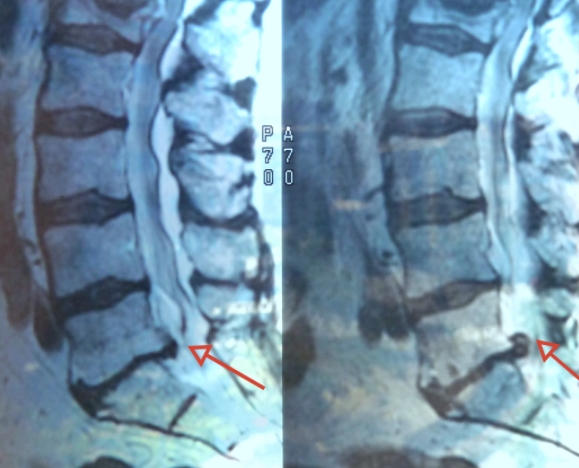

척추는 추골이라 불리는 뼈가 연결되어 이루어져 있습니다. 그런데 나이를 먹으면서 노화와 함께 추골에 있는 척추관이라 불리는 신경이 통과하는 길이 좁아지게 됩니다. 이렇게 좁아지게 되면 그 안을 통과하고 있는 신경이 압박을 받아서 허리통증과 엉덩이, 다리가 저리는 증상 까지도 나타나게 됩니다.

노화 등의 영향으로 추간판이나 요추가 변형 변성되어 척추관이 좁아지면 그 안을 통과하는 마미신경이 압박을 받게 됩니다. 마미신경이란 다리쪽 신경을 조절하는 신경입니다. 그런데 이 부분이 압박을 받으면 신경이 영향을 받아 다리에까지 통증이 나타나고 저리는 등의 척추관 협착증 증상 보이게 됩니다.

척추관 협착증 이란 노화로 인한 변화로 추간판 변성과 뼈 변형, 인대가 늘어나는 등의 여러가지 증상의 원인이 되기도 합니다. 하지만 이런 협착증 증상 이라는 것이 하지의 혈전성 정맥류, 동맥경화증 등 혈류장애질환의 증상과도 비슷하기 때문에 정확한 진단을 받아야 합니다. 허리 디스크와의 차이는 잘 걸리는 연령대로 먼저 추측을 해 볼 수는 있습니다.

그리고 척추관 협착증 으로 인한 허리통증 자체는 허리 디스크의 통증에 비교하면 그렇게 심하다고는 할 수 없습니다. 하지만 등을 쭉 펴고 서거나 걷거나 하는 등의 척추관이 좁아지는 자세를 취하면 마미신경이 더 압박을 받아 하지가 저리고 다리 움직임이 나빠지게 됩니다.